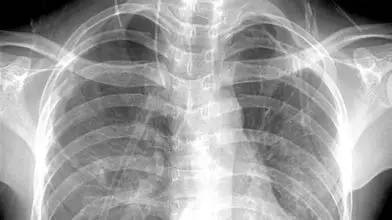

3、胸部——粗看X光片,細看CT

X光胸片可粗略檢查心臟、主動脈、肺、胸膜、肋骨等,可以檢查有無肺紋理增多、肺部鈣化點、主動脈結(jié)鈣化等。

胸部CT檢查顯示出的結(jié)構(gòu)更清晰,對胸部病變檢出敏感性和顯示病變的準確性均優(yōu)于常規(guī)X光胸片,特別是對于早期肺癌確診有決定性意義。但是CT檢查的輻射劑量高于X光。核磁對于肺部疾病的診斷,應(yīng)用非常有限。